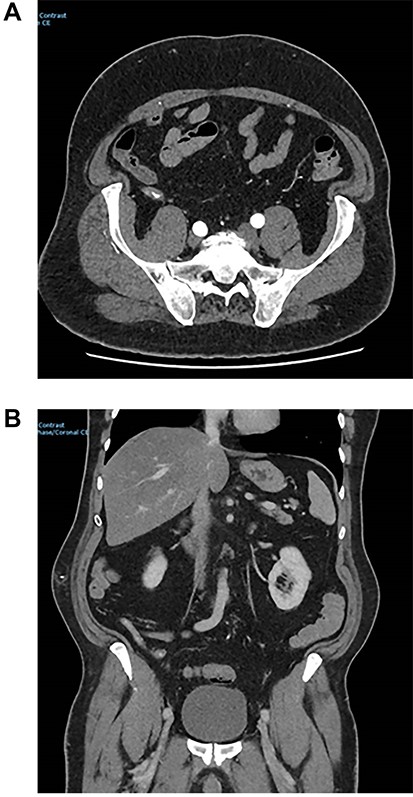

During initial surgical assessment, the patient identified that he was a practicing Jehovah’s Witness and would not accept blood products, even if that would result in a poor outcome, including death. The patient was therefore resuscitated intravenously with crystalloids as per his expressed wishes and underwent a CT angiogram to investigate the cause of the bleeding. CT scan demonstrated active bleeding in the caecum/appendix with an obvious blush noted (Fig. 1).

Images from angiography. (A) Pre-embolization, demonstrates appendiceal lumen filled with contrast. (B) Demonstrated coiled artery.